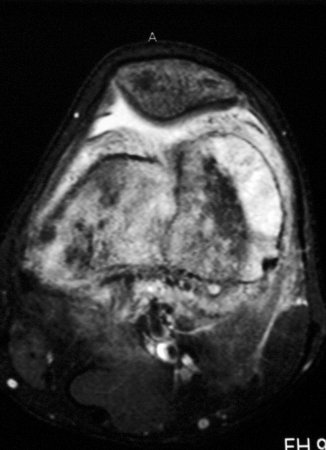

[Figure caption and citation for the preceding image starts]: Magnetic resonance imaging, axial view; osteosarcoma of distal femur showing high-intensity signal; T2-weighted imagePersonal collections of Dr Michael J. Klein and Dr Luminita Rezeanu [Citation ends].

low signal on T1-weighted images; high signal on T2-weighted images; fluid levels